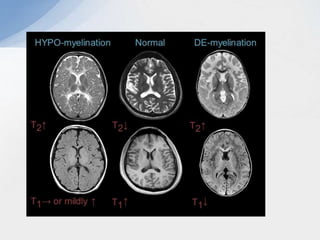

De-myelination Vs hypo-myelination

Demyelination:

• Prominent T2 hyperintensity.

• Prominent T1 hypointensity.

Hypomyelination:

• Mild T2 hyperintensity.

• Variable T1 signal (hypo, iso or hyperintense).